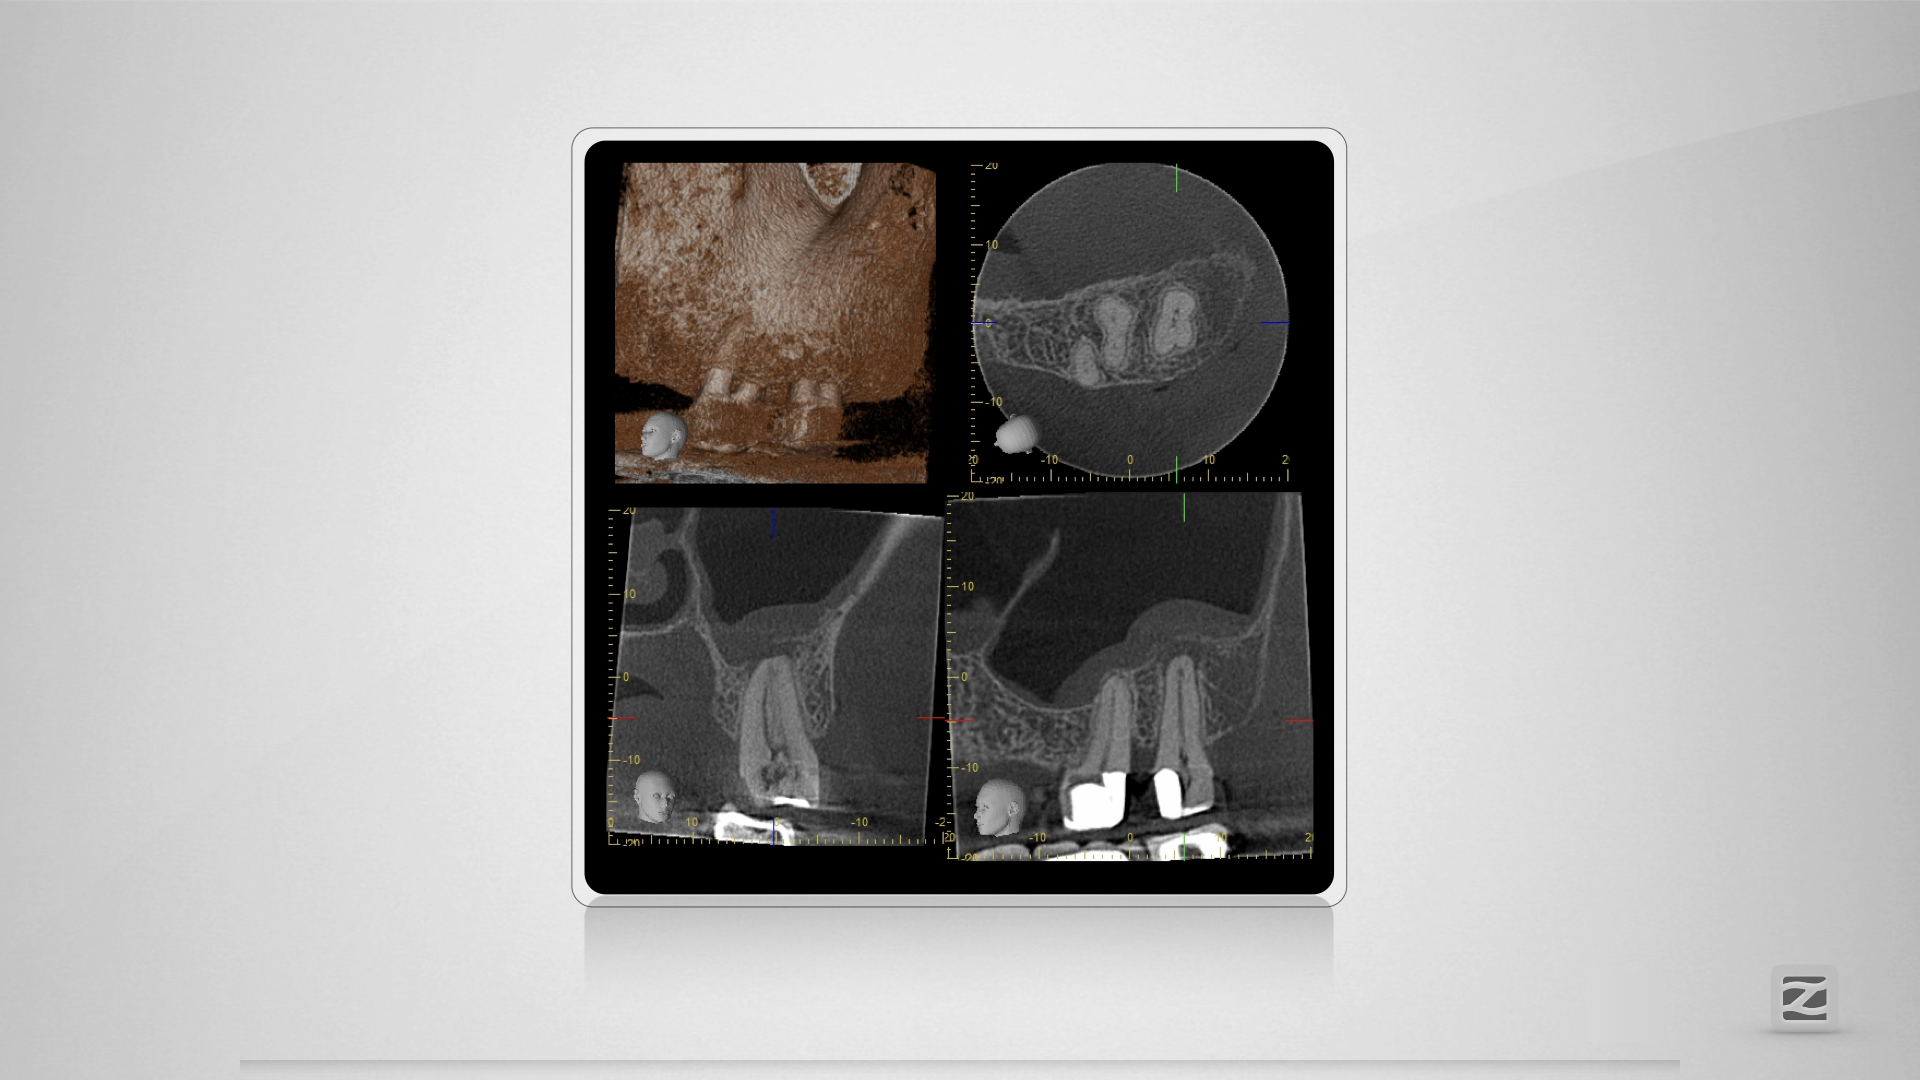

27D.004

Großer Dentikel, tiefer Split.